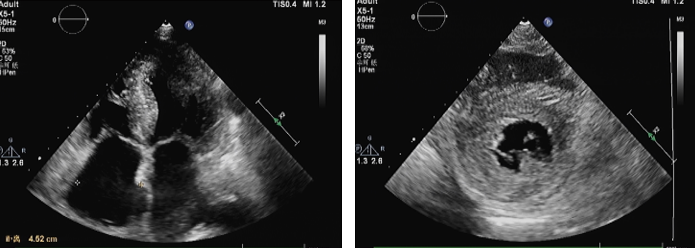

超声心动图:

舒张功能进行性恶化;左室对称增厚;在非扩张型心室的情况下对称增加的双心室壁厚度(LV壁厚> 12 mm且通常> 15 mm)。二维斑点追踪技术整体纵向应变(global longitudinal strain, GLS) 左心室最为可靠的应变指标,但不能区分淀粉样变类型。